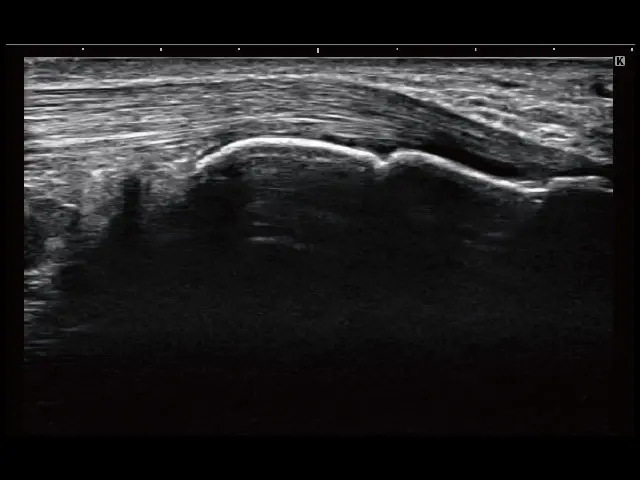

イメージギャラリー

イメージ画像を表示する